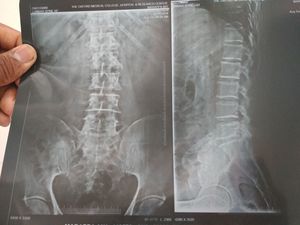

What are your diagnosis??

Sacralisation of lumbar vertebrae..?

Flat back syndrome - due to the loss of curvature to the Lumbar spine?

Lumbar curvature defect?

Sacralisation of lumbar vertebra